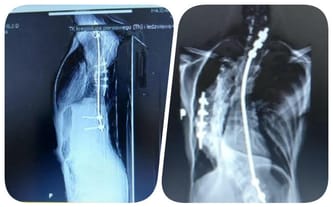

Mój problem ze skoliozą zaczął się w wieku 4 lat, gdy złamałam nogę i po 6 tygodniach na wyciągu moje plecy się skrzywiły. Lekarze uspokajali jednak, że garb się wchłonie. Jednak tak się nie stało i skrzywienie coraz bardziej się pogłębiło.

Zaczęły się rehabilitacje, basen i gorsety, które miały mi pomóc, jednak jak się później okazało, pogłębiły skrzywienie. Od czasu pierwszej operacji chodzę w plastikowym gorsecie, który bardzo utrudnia mi codzienność. Chciałabym żyć chociaż w miarę normalnie...

W wieku 12 lat trafiłam do lekarza, który powiedział, że wyprostuje moje plecy. Niestety z 2 operacji, tak jak zapowiadał, zrobiło się 13. Pręty w moich plecach co chwilę pękały... Po operacji wróciłam do domu i tego samego dnia pręt pękł i znowu musiałam wracać do szpitala na kolejną operację.

Pojechałam na konsultację i podczas niej otrzymałam kolejny cios od losu, potrzebna jeszcze jedna operacja. Implanty, które mam prędzej czy później pękną i mogą przebić organy wewnętrzne. Moje płuco jest bardzo uciśnięte przez skrzywienie i może przestać pracować...

Bardzo bałam się, że nikt nie będzie chciał mnie naprawić i będę musiała chodzić z tykającą bombą. Na szczęście znalazł się lekarz, który podejmie się operacji. Niestety może wykonać ją tylko prywatnie, a to generuje ogromny koszt! Pomoc jest w zasięgu ręki, ale potrzebuję wsparcia dobrych ludzi. Proszę, podaj mi pomocną dłoń i pozwól mi żyć normalnie i bez strachu...